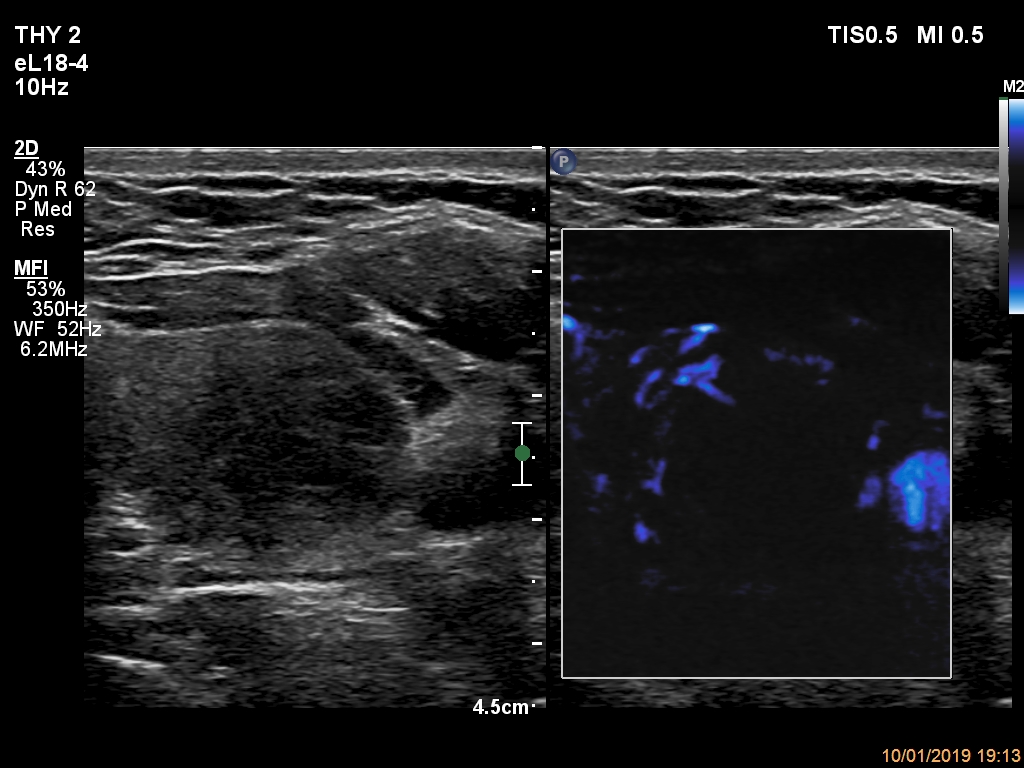

Examination a year later (ultrasonographic picture 5)

Left lobe, transverse scan, microflow imaging. There are several vessels in the medial and in the lateral part of the nodule.